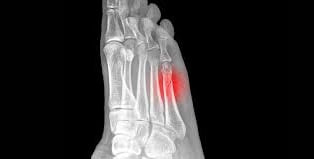

Stress Fractures

A stress fracture is a small crack in a bone, or severe bruising within a bone. Most stress fractures are caused by overuse and repetitive activity; they are common in runners and athletes who participate in running-intensive sports, such as soccer and basketball.